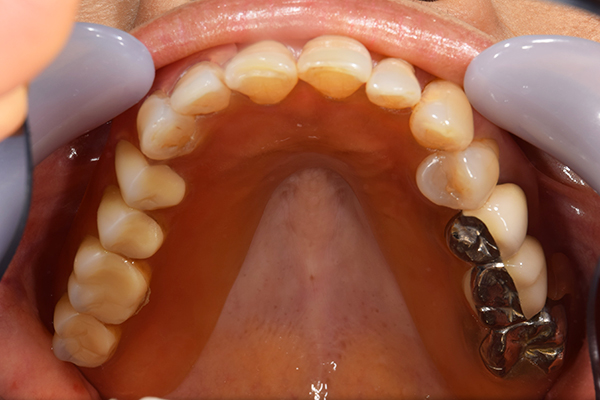

ケース1(自費の部分入れ歯)

前歯が折れて当院にいらっしゃいました。 過去に下の入れ歯を作ったが、合わなくなってずっと入れ歯をいれていらっしゃらない患者様でした。 これは奥歯で噛むことができないため、前歯で噛むことを繰り返したために、負担に耐えられなくなった前歯が折れてかぶせ物ごと 外れてしまったのだと考えられます。 痛くない、違和感の少ない、下の入れ歯を作ることがこの方のゴールであると考えられました。

シリコンで精密な型取りを行いました。

噛み合わせチェックです。 奥歯でしっかりものが噛める様に高さを決めていきました。

金属を使用して、薄く違和感が少ない入れ歯が完成しました。 また、見た目にも気を使い、バネが見えにくい様な構造にしました。

入れ歯をお口の中にいれた状態です。前歯もMTMといって、歯を少し引っ張り出す処置を行なったことで、しっかり残せて、またかぶせ物をしました。

年齢 70歳・女性

主訴 前歯が取れた

治療期間 8ヶ月

治療費 .MTM:110,000円

.ファイバーコア:16,500円

.E-maxクラウン:110,000円

.義歯:660,000円

治療方針 長年使ってきた義歯の人工歯が磨耗し、臼歯部での咬合がすくなくなり、前歯部での接触が強くなったことで生じた前歯の破折なので、義歯も作り変える必要がある。

治療内容 前歯部MTMと同時に審美面の回復。

MTM中に義歯の作成も同時に行う。

最終的に義歯と前歯のクラウンを同時にいれる。

義歯は下顎で、しっかり噛めること、違和感の少ないものという希望があったため、なるべく入れ歯を薄く作成するために金属をしようした義歯とした。

また、見た目もあまり義歯が目立たない様に、バネの部分を見えにくいように作成した。

特記事項 歯にもともと入っていた金属の種類によっては、歯自体の変色を治療で変えられないこともある。 義歯は作ってから痛みがでることがありますが、それは調整を行うことで痛くなくすることができます。